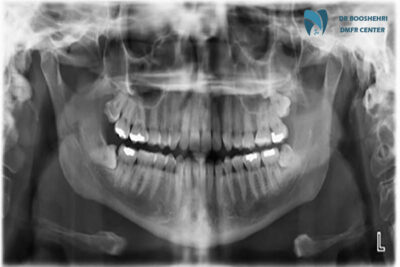

In maxillofacial radiology, extraoral radiography is one of the main tools for examining complex problems. This method helps dentists and maxillofacial surgeons obtain a comprehensive view of the jaws, sinuses, and jaw joints. Panoramic, cephalometric, and CBCT imaging are examples of extraoral imaging techniques, each with specific applications.

Panoramic imaging is a type of extraoral radiography. This method provides a view of the entire upper and lower jaws, teeth, jaw joints, and sinuses in a single image. Panoramic imaging is especially useful for examining structural abnormalities, impacted teeth, and tumors.